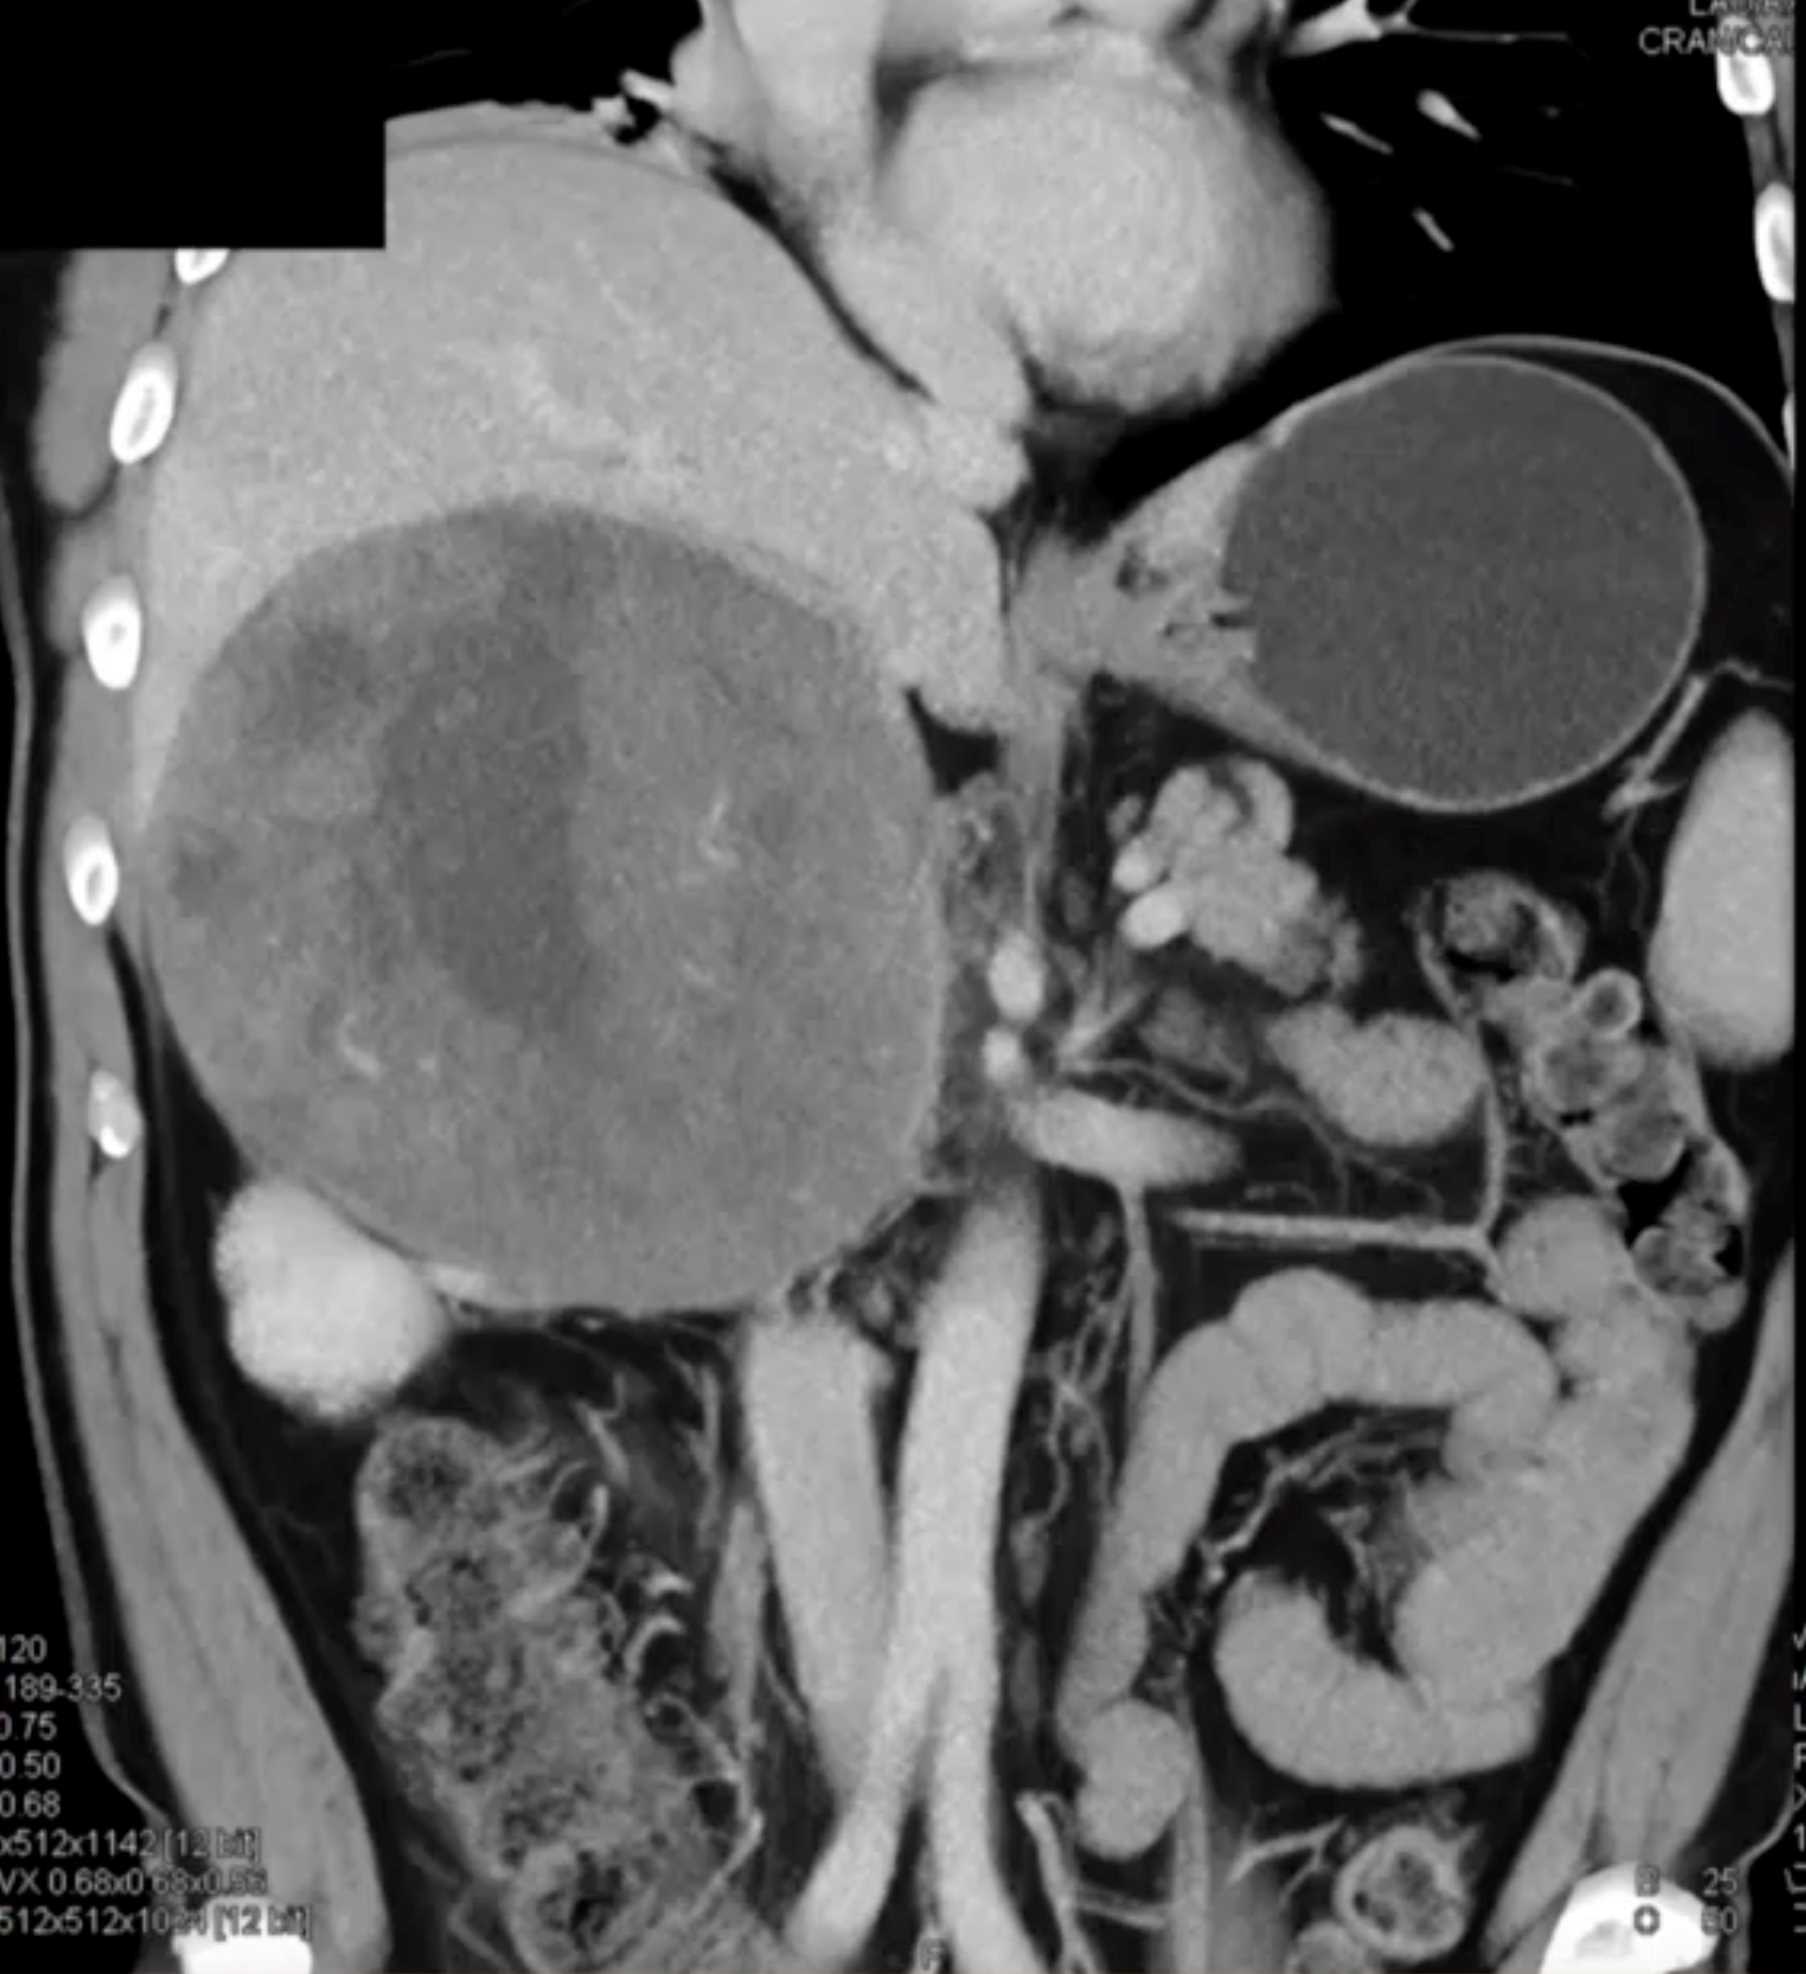

Left Adrenal Metastases from Renal Cell Carcinoma